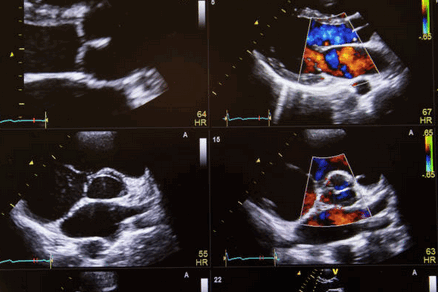

Адекватную визуализацию легочных венозных соединений необходимо получить из нескольких плоскостей визуализации. У младенцев и детей, надгрудинная коронарная плоскость сканирования с задней ангуляцией может продемонстрировать позицию «краб», из которой можно посмотреть, что происходит с соединениями из четырех легочных вен у корпуса левого предсердия (или венозном впадение при ПАДЛВ). Однако, потенциал для множественных соединений сосуществует в таком пациенте, что делает усердный поиск легочных вен довольно трудным, поэтому врач на эхокардиографии использует все имеющиеся плоскости, обязательные в этих случаях.

В нормальном сердце, апикальная четырехкамерная позиция на УЗИ сердца показывает связи правой и левой нижних легочных вен на задней и нижней области левого предсердия (ЛП). Субкостальная четырехкамерная и сагиттальное сканирование позволяет визуализировать соединения правой верхней легочной вены в ЛП. Кроме того, из этих позиций, может быть визуализирован дефект венозного синуса. Левую верхнюю легочную вену часто можно увидеть в парастернальной короткой оси или из надгрудинного сканирования, описанного выше. У пациентов с увеличением правого сердца, сканирование с правой паразитарной области часто обеспечивают четкое изображение предсердий перегородки и легочных вен.

Если вход всех легочных вен в ЛП не визуализируется уверенно, необходимо провести исчерпывающий поиск для оценки возможных аномальных связей. Это часто одна из самых сложных задач при врожденных пороках сердца в эхокардиографии. Чреспищеводная эхокардиография (ЧПЭХОКГ) полезна в определении дренажа правых легочных вен, даже когда они аномальны. ЧПЭХОКГ должна быть использована в случаях необъяснимого расширения правого предсердия для того, чтобы исключить ЧАДЛВ.